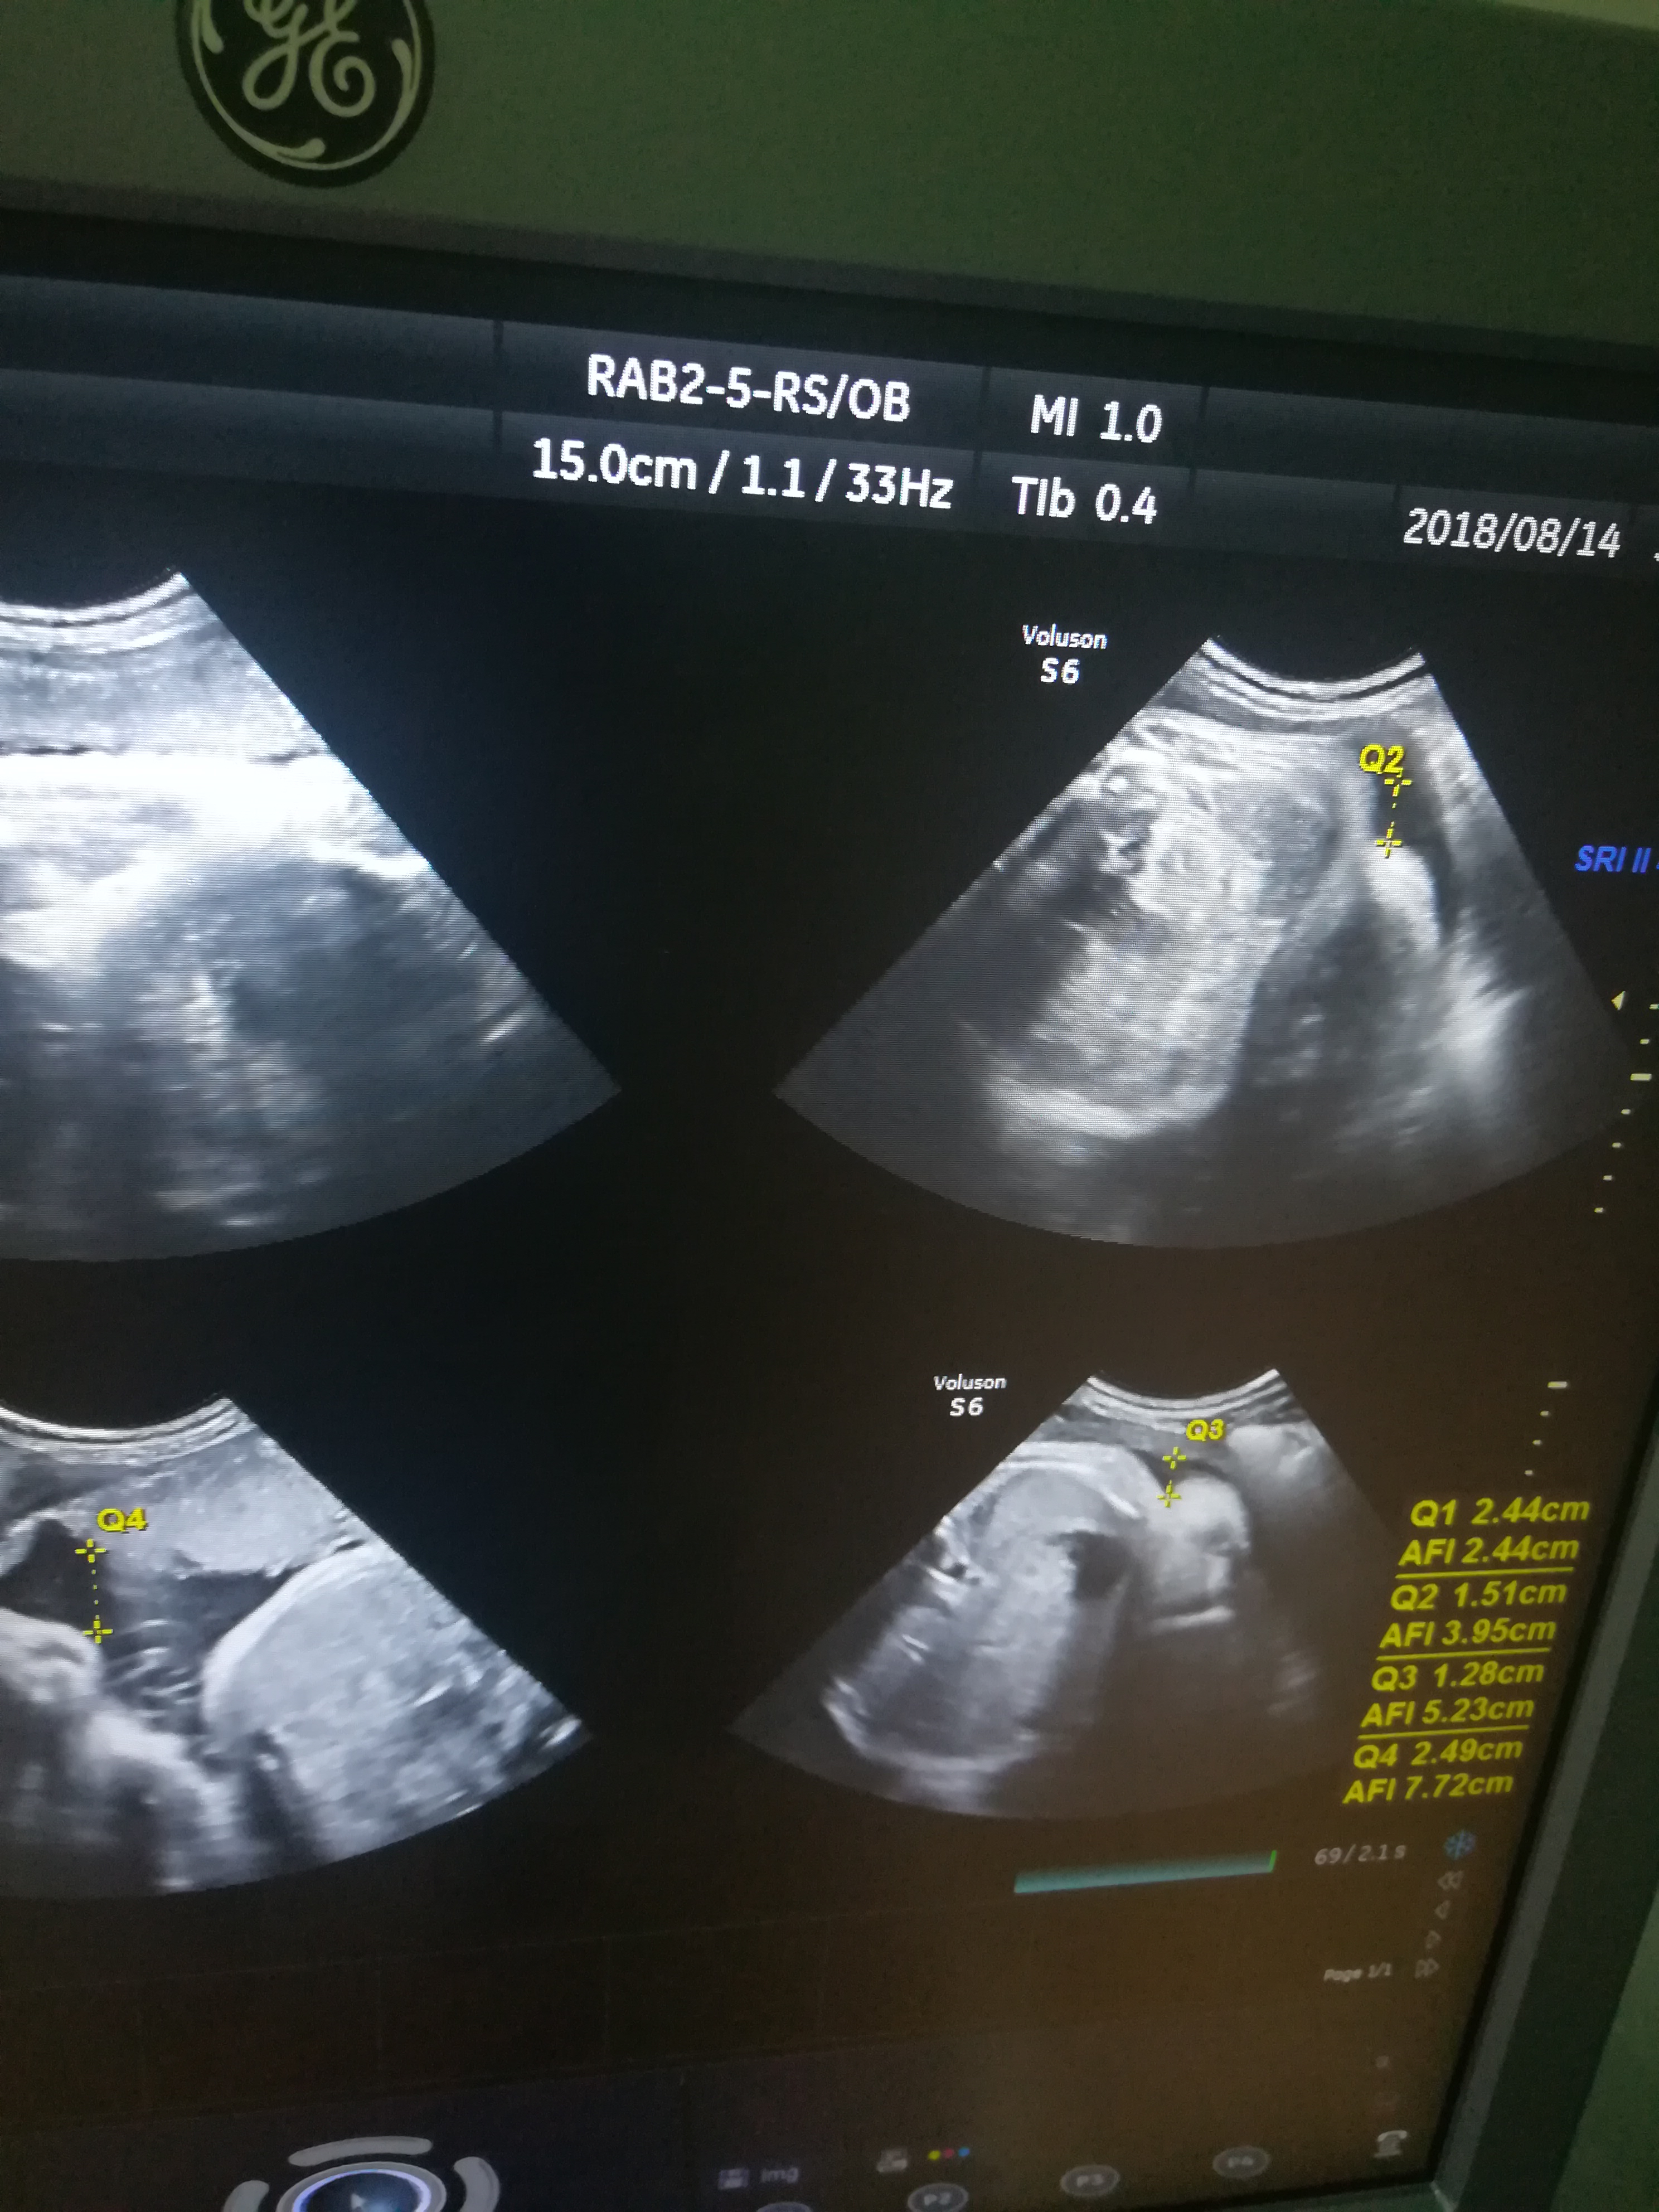

叫朋友找b超的人照的,他就照了这样的数据给我,我看不懂,他又下班了,所以没有问到情况,哪位看的懂的,麻烦帮我解释一下

第一张是羊水量。第二张是四肢的长度吧